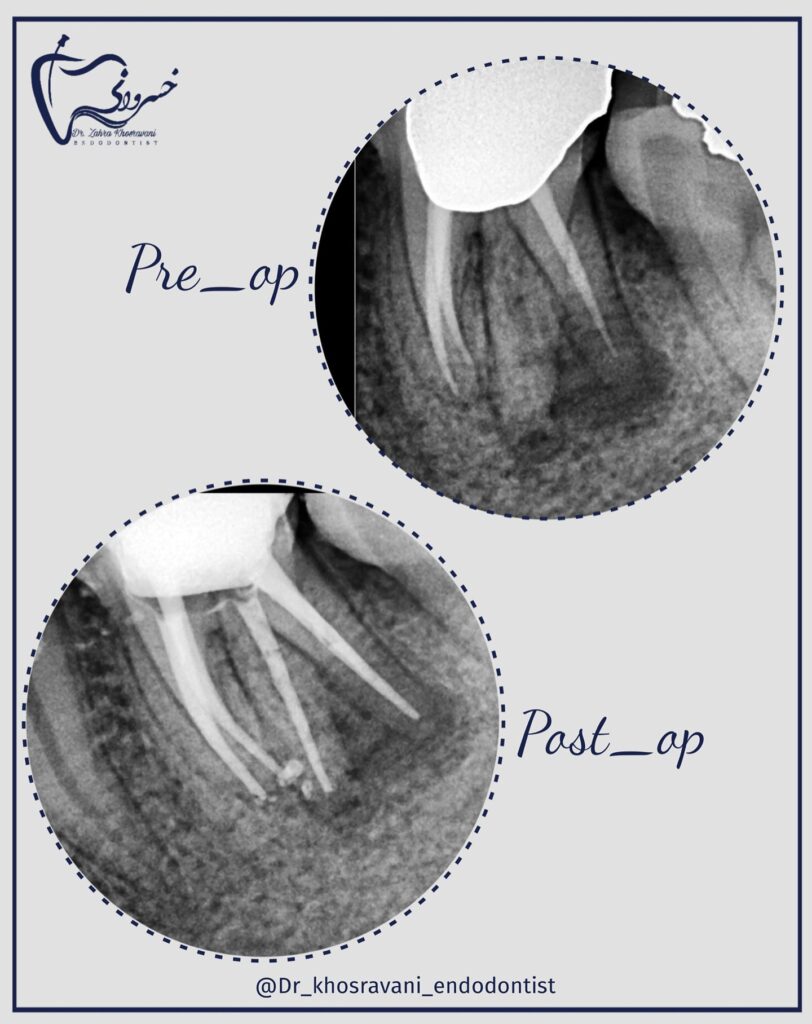

درمان ریشه

درمان ریشه دندان مولر اول پایه بریج